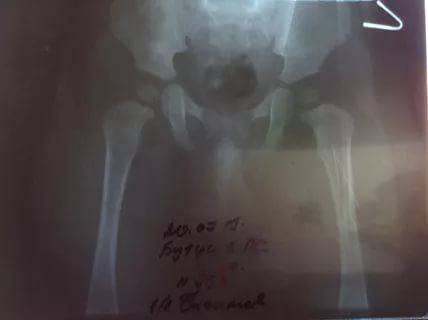

У этой собаки умеренные изменения, указывающие на дисплазию бедра с обеих сторон.

Гнезда не такие закругленные, как должны быть, а головка бедренной кости немного приплюснута.

У этой собаки дисплазия тазобедренного сустава в правом тазобедренном суставе (см. Маркер R справа)

Это тяжелый случай двусторонней дисплазии тазобедренного сустава

Это тяжелая дисплазия тазобедренного сустава